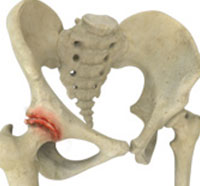

Femoroacetabular impingement (FAI) is a condition where there is too much friction in the hip joint from bony irregularities causing pain and decreased the range of hip motion. The femoral head and acetabulum rub against each other creating damage and pain to the hip joint.